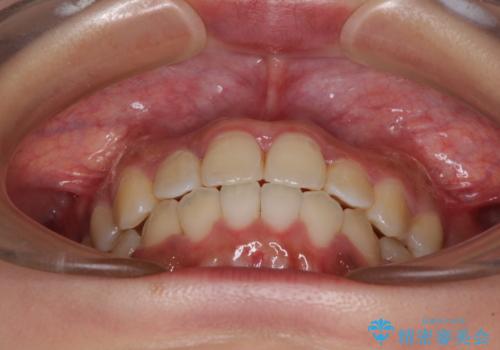

前後に重なった前歯 ワイヤー装置と急速拡大装置を併用したインビザライン矯正

急速拡大装置による上顎骨の側方拡大が思った以上にうまくいき、非抜歯での矯正が可能となりました。

内側に倒れていた下顎の臼歯は起き上がり、清掃性も大幅に改善されました。